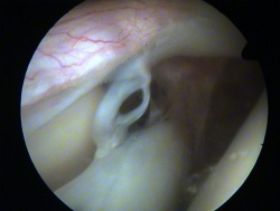

SLAP III : uszkodzenie obrąbka tzw. rączka od wiaderka , z przemieszczeniem części obrąbka , ale bez uszkodzenia przyczepu LBT (bicepsa)

SLAP III podczas artroskopii